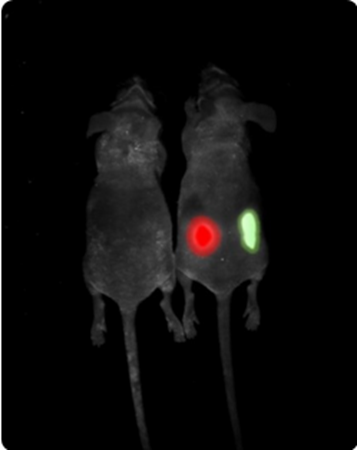

Multispectral in vivo imaging

Different fluorescent dyes or luciferase enzyme/substrate pairings allow multispectral in vivo imaging. Up to three signals can be superimposed on the same image.

Multispectral imaging. Image Credit: Scintica Instrumentation Inc